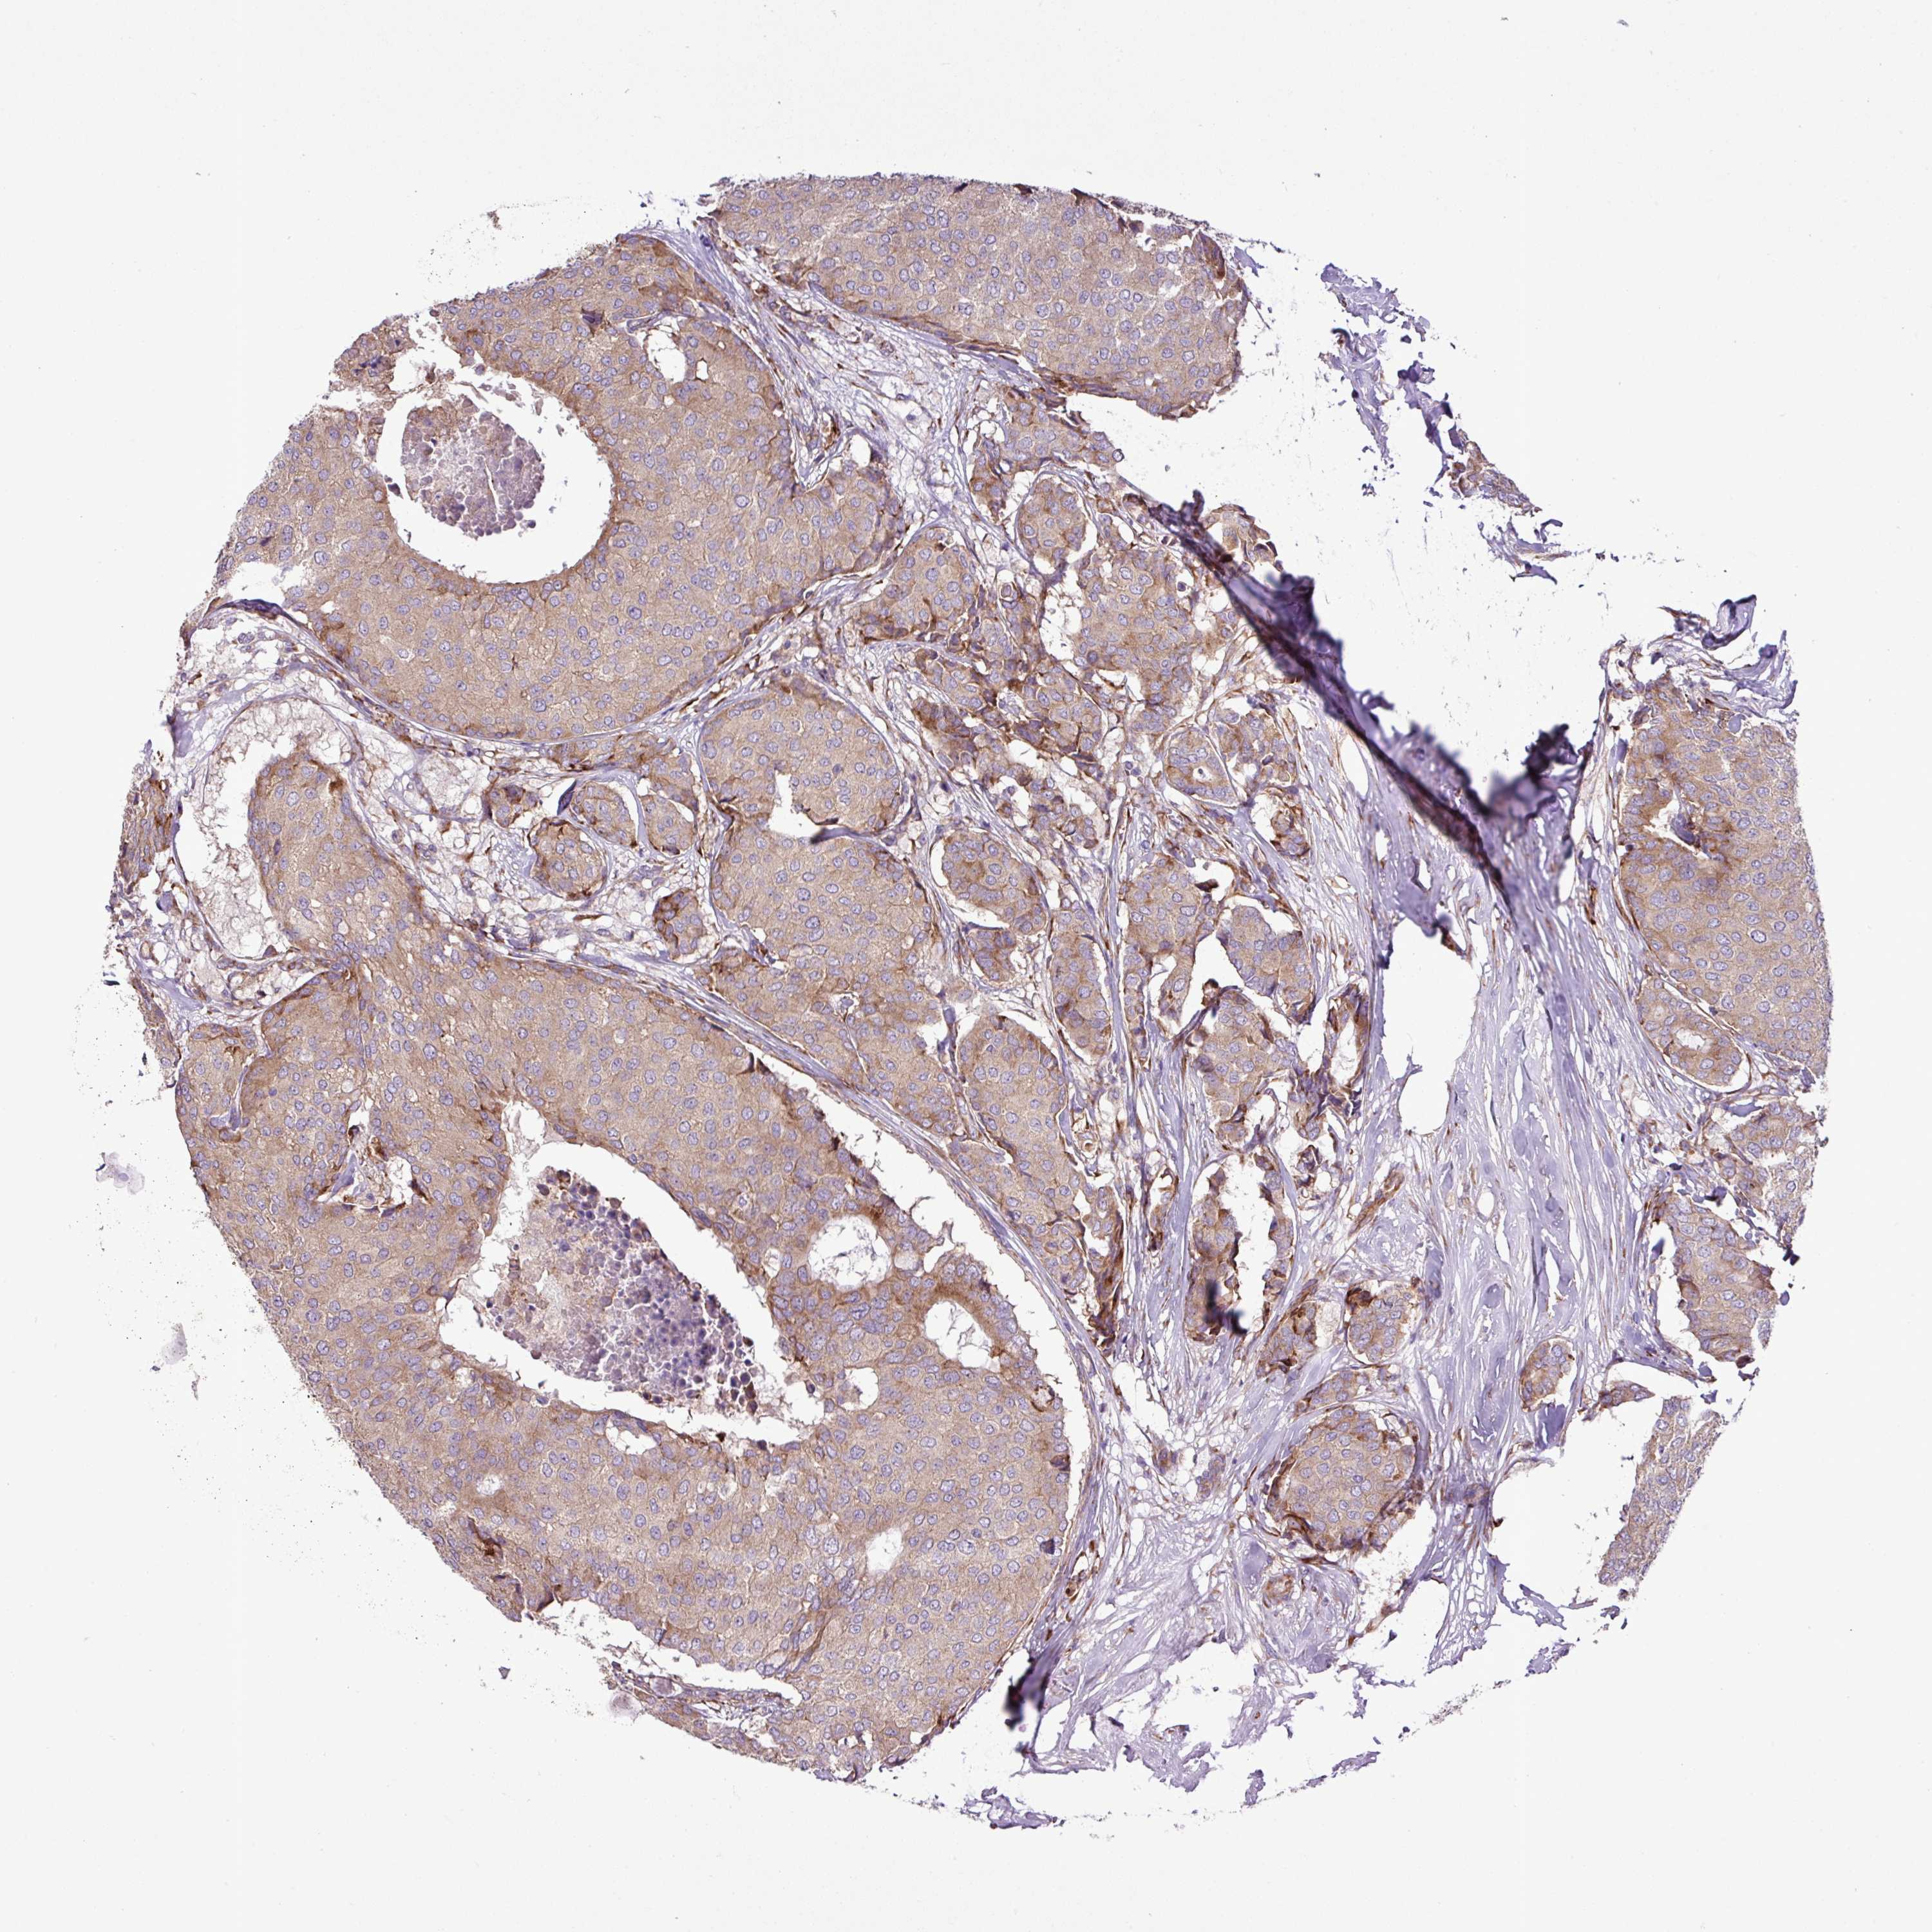

CANCER BREAST CANCER Show tissue menu

BRCA TCGA BRCA VALIDATION PROTEIN EXPRESSION